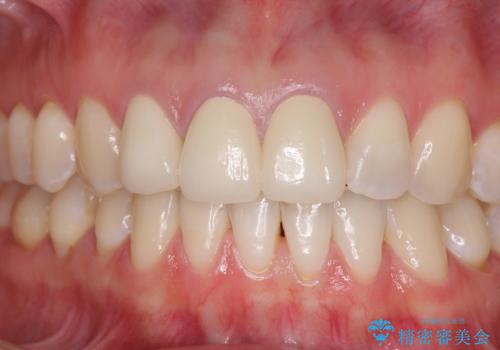

ゴールドインレーは銀歯のインレーやセラミックインレーと比べ、「技工操作の精度が高く、適合が著しく良い」というメリットがあります。特に上の奥歯は歯科医師の操作が行いにくいため、「適合の良さ」は再治療のリスクを防ぐ上でとても重要な要素となります。

上の奥歯は金属色が見えることもないため、審美的な問題は全くありません。

咬み心地はとても良好で、全く違和感がなく、患者様には大変満足していただきました。